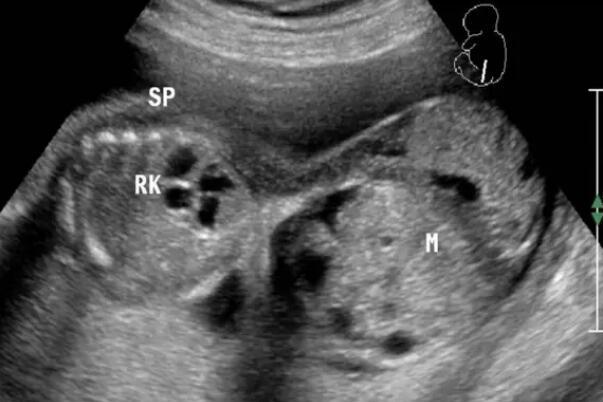

做畸胎瘤手术最佳时期是什么时候?畸胎瘤是一种影响女性健康的卵巢疾病,我们一定要治疗。一般手术是常规治疗方法。那么做畸胎瘤手术最佳时期是什么时候?

一般情况下畸胎瘤太小就不建议手术。因为如果<3cm的卵巢畸胎瘤,手术在腹腔镜下,需要把正常的卵巢组织切开,去找到小小的卵巢畸胎瘤,把畸胎瘤剥除。

这个手术过程就有可能对正常的卵巢组织造成致命性的损伤,尤其是对正常的卵巢血供造成致命性的影响,影响以后的卵巢功能,影响卵巢的排卵功能,甚至有可能导致卵巢早衰,所以特别小的畸胎瘤不建议手术。一般考虑畸胎瘤达到直径5cm的时候,这个时候做腹腔镜,可以很容易地发现畸胎瘤在哪。可以不去损伤很多正常卵巢组织的情况下,把卵巢的畸胎瘤完整的剥除,这个时候是最佳的卵巢畸胎瘤的手术时机。

畸胎瘤微创手术的过程,卵巢畸胎瘤由于95%以上的都是良性肿瘤,所以可以通过手术剥除,而达到治疗的效果。目前对卵巢畸胎瘤的手术多采用腹腔镜操作。

腹腔镜就是在腹壁,打上3-4个直径1cm或0.5cm的小洞,将操作器械放到腹腔内,从卵巢上剥除畸胎瘤,然后再将剥下来的肿瘤,放在取物袋内,将取物袋的开口提到腹壁外,捣碎囊内的肿瘤,再将它取出来进行病理检查。如果报告是良性的畸胎瘤,对卵巢进行止血和整形以后冲洗腹腔,手术就可以结束。总的来讲,对卵巢畸胎瘤的微创手术,主要是通过腹腔镜进行肿瘤的剥除、取出,以及修复卵巢这样的操作过程。